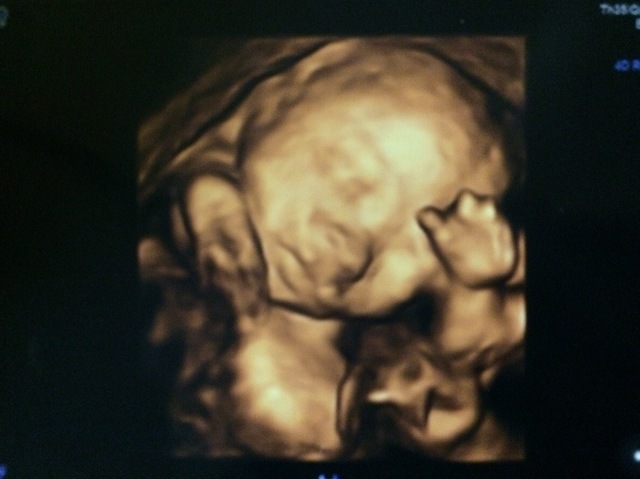

22週0日(22w0d・女の子)|rico136jr さん(28歳)

エコー写真撮影時のエピソード:

この日はじめて、こんなにはっきりと顔が見えるエコー写真を撮っていただけました。はじめは手で顔を隠していましたが、少し経ってからまた見ると、しっかりお顔を見せてくれていました。はじめて旦那さんが検診についてきてくれた日でもあり、エコーのあいだずっと夫婦2人で可愛い可愛いとデレデレになってしまいました。旦那さんはそれまであんまり赤ちゃんに興味ない様子だったのですが、この日以来、急にこの写真を出してきては「可愛い〜絶対美人になるね」「鼻はママ似かな?」など、本当にメロメロになってくれているのがまた愛おしいです。家族にも見せたところ、すごく感動してくれました。体調面では特に問題なく、栄養価の高いものを摂るようにはしていますが、つわりが酷かった分、食べたいものが食べられる幸せを噛みしめ、旦那さんと近場の県への国内旅行を楽しんでいます。そろそろ後期に入るので、食事や生活に気をつけて、出産準備をしていきたいと思います。